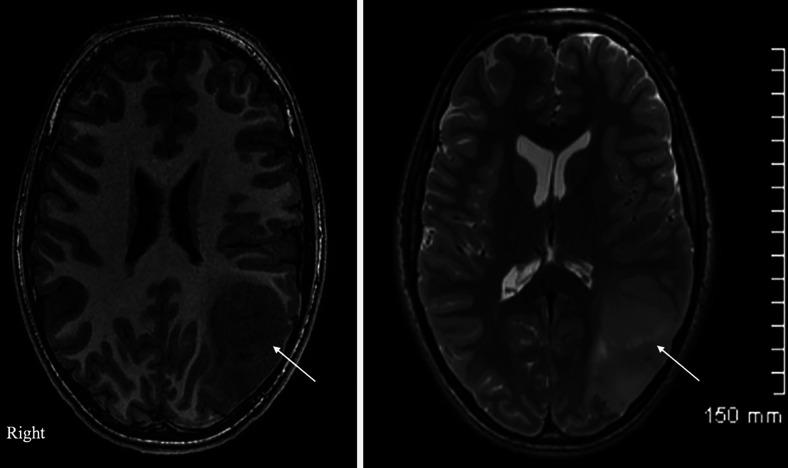

A 13-year-old bilingual male with glioblastoma multiforme involving the left parietal lobe and deep occipital white matter underwent preoperative language mapping using magnetic resonance imaging-guided TMS. Language-specific cortices were successfully identified in both hemispheres. TMS findings aided in discussing with the family the risks of postsurgical deficits of tumor resection; postoperatively, the patient had intact bilingual speech and was referred for chemotherapy and radiation.

一名13岁的双语男性患有多形性胶质母细胞瘤,累及左顶叶和枕叶深部白质,在磁共振成像引导下使用TMS进行了术前语言定位。在两个半球均成功识别出特定语言的皮质。TMS结果有助于与家属讨论肿瘤切除术后出现功能缺陷的风险;术后,患者的双语言语功能完好,并被转诊接受化疗和放疗。